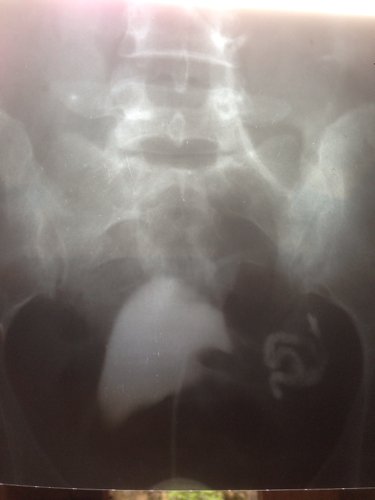

输卵管切了一边 请问另一边通畅吗 点击展开 匿名用户 2013-11-06 14:50 为您推荐: 其他回答 病情分析: 您好,如果未切除的输卵管没有堵塞问题,就能正常发挥其自身功能。 指导意见: 导致输卵管堵塞的因素有多种,可以向帮您检查治疗过的医生咨询治疗后的状况。 匿名用户 2013-11-06 15:00 相关问题 切了一边输卵管另一边伞端欠通畅 您好医生!我想咨询一下,我六月份查出输卵管一边堵一边通畅不良,医生给我开了胎盘片和促排卵的针,请问 孕育 一边输卵管切除,另一边又可能宫外孕了,以后是该要怎么生育好呢?现在怀孕34天,隔三天测了两